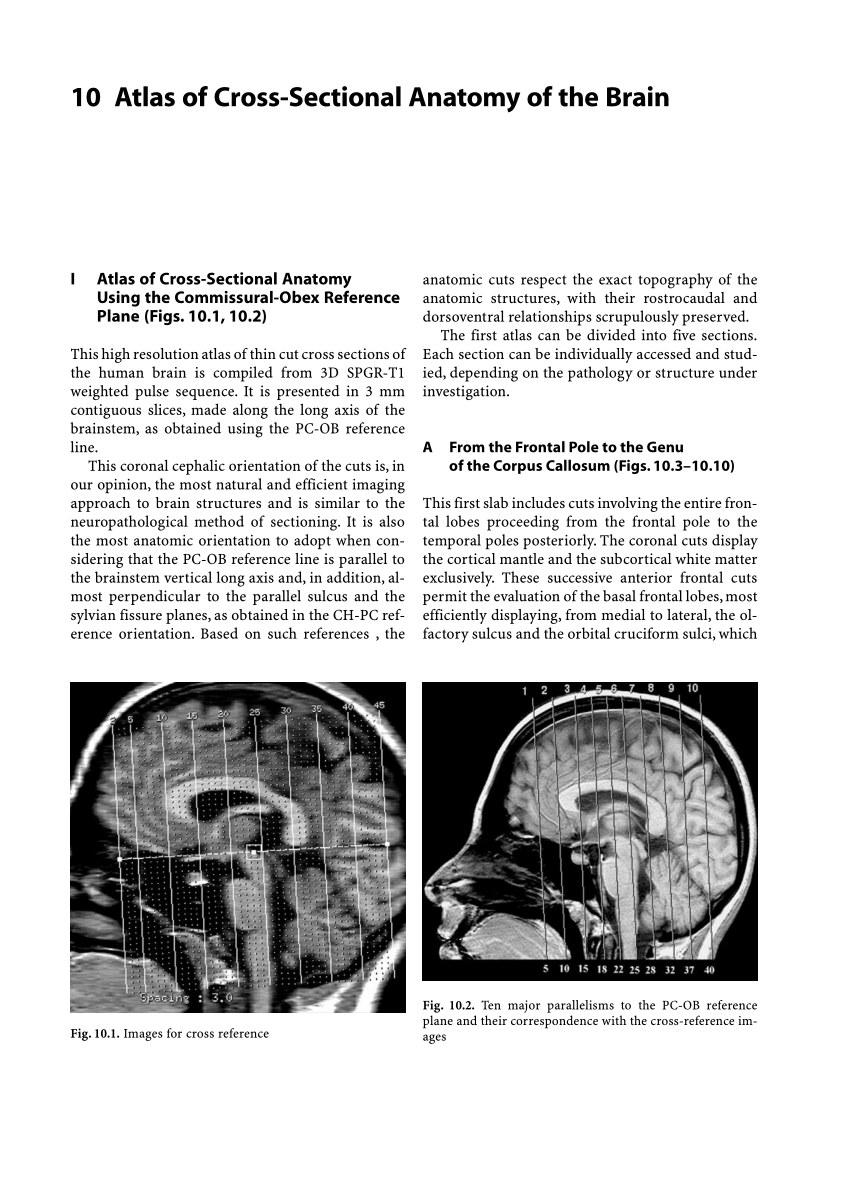

Pdf Atlas Of Cross Sectional Anatomy Of The Brain

Pdf Atlas Of Cross Sectional Anatomy Of The Brain